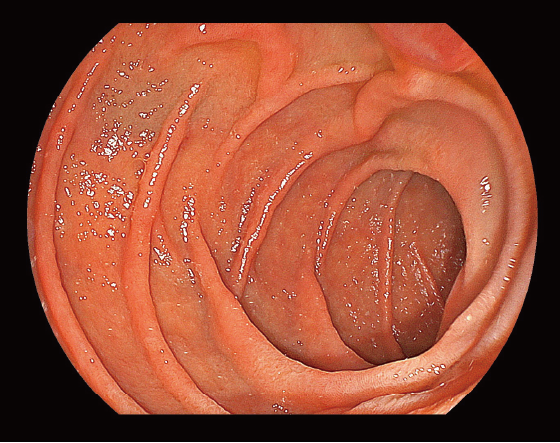

Compared to the conventional endoscopes*2, the sensors integrated in the 800 system endoscopes enable to image with less noise.

- *1 It may differ from actual image

- *2 760 series endoscopes